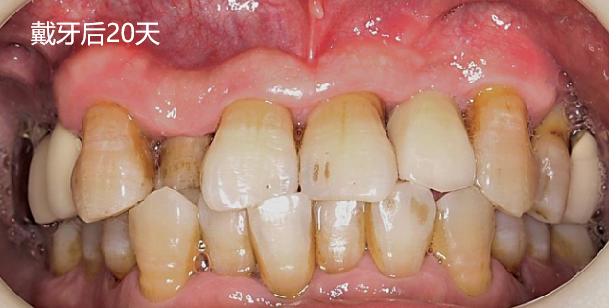

戴牙后20天复查X线检查

术前术后对比

由于患者需求因素未进行“即刻临时修复体”的制作和个性化过度义齿试戴,一定程度上影响了术后美学效果的提升。

修复阶段,使用个性化印模制备模型,订制个性化基台螺丝固位,改变了患牙原始的反合情况,尽量纠正为浅覆盖,美观方面有所提升。